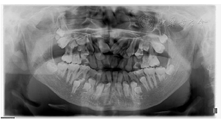

畸形(图1)。(2)口内检查:混合牙列,31、41、16、26、36、46萌出,37、47部分萌出,剩余乳牙滞留;54、64远中邻

面龋,探(-),叩(+),松0-I°,龈正常;全牙列反

,反覆盖10mm,双侧尖牙及磨牙近中关系;51、61扭转,上颌牙弓狭窄,腭盖高拱,31、41间可见间隙约5mm(图2)。(3)影像学检查:①曲面断层片示多数乳牙滞留,恒牙迟萌,多颗埋伏阻生多生牙。54、64远中邻面低密度影及髓,牙根吸收(图3);②CBCT示全口恒牙排列紊乱,上下颌骨内可见13颗多生牙,均位于恒牙胚舌腭侧,形态类似相邻恒牙胚(图4);③头颅侧位片示头颅侧位片示上颌骨发育不足(NA-Apo:-5.9°),下颌前突(SNB: 98.2°;FH-NPo:90.0°),骨性III类错